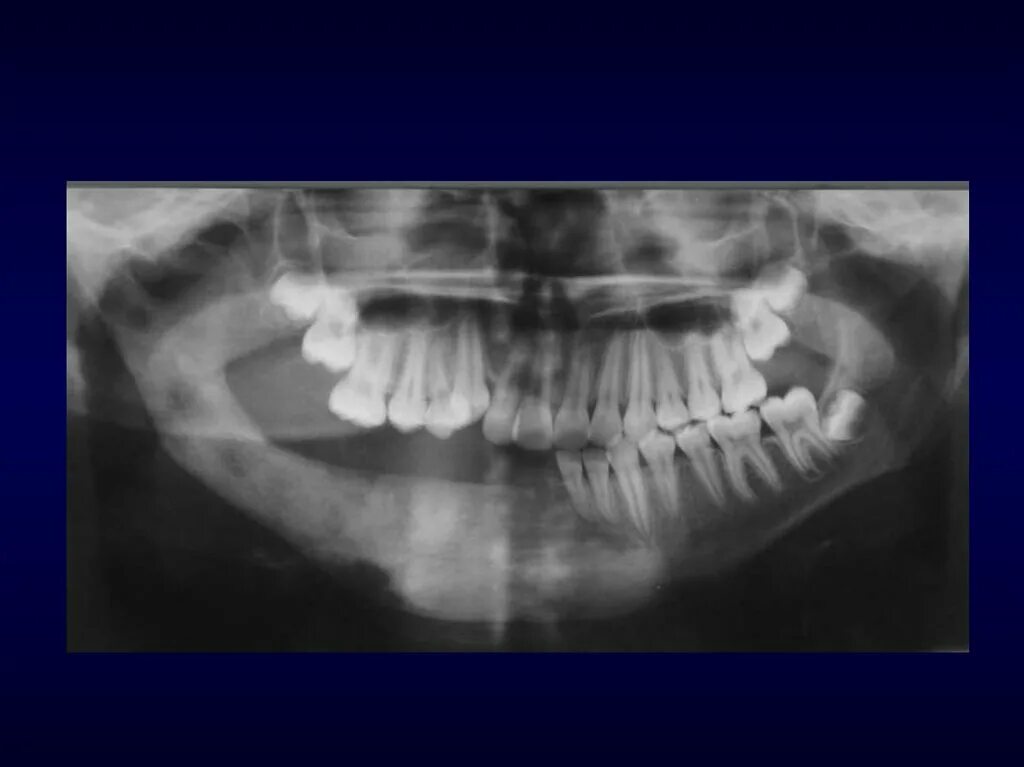

Одонтогенный остеомиелит челюсти. остеомиелит верх челюсти. хронический остеомиелит челюсти снимок. одонтогенного остеомиелита челюстей.

Одонтогенного остеомиелита. одонтогенный остеомиелит нижнечелюстной. остеомиелит верхней челюсти кт. острый остеомиелит верхней челюсти.

Подострая одонтогенного остеомиелита.. одонтогенный остеомиелит рентген. остеомиелит челюсти рентген. одонтогенный остеомиелит челюсти рентген.

Одонтогенный остеомиелит рентген. хронический остеомиелит челюсти. клиника острого остеомиелита нижней челюсти. муфтообразный инфильтрат.